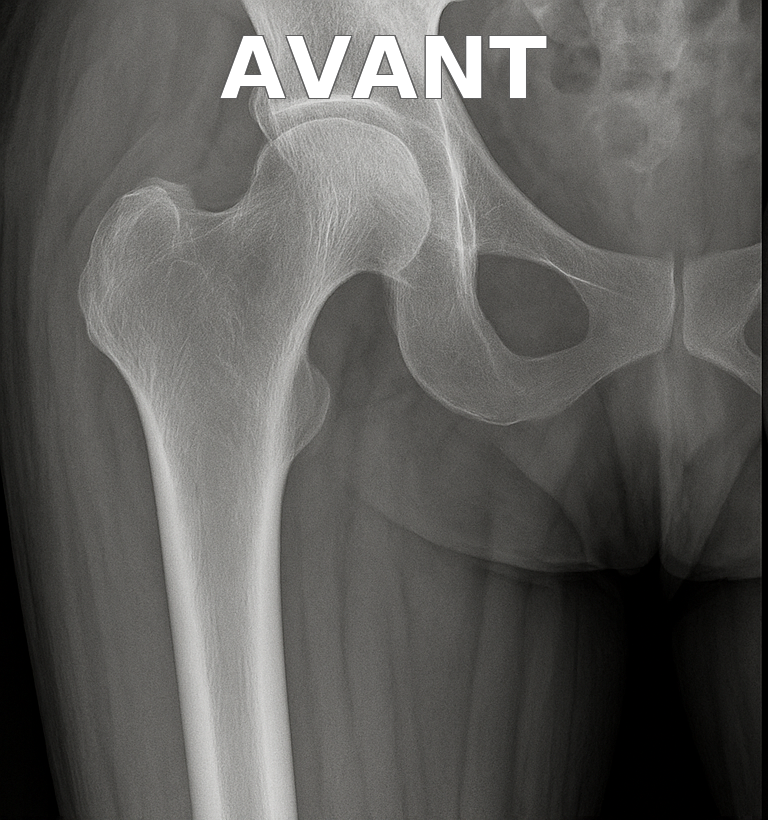

Prothèse de hanche